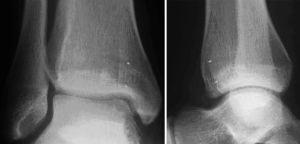

* RMN para determinar la extensión y localización de la lesión (fig. 1).

Figura 1. RMN de tobillo en la que se observa una lesión osteocondral de la porción posterior del astrágalo.

A los seis meses de la cirugía la RMN ya mostraba una buena integración del bloque óseo y del cilindro implantado. Concretamente a nivel de la tibia, no se encontraron edema perifocal, vetas de esclerosis, ni incongruencia de las superficies articulares (fig. 15).

Figura 15